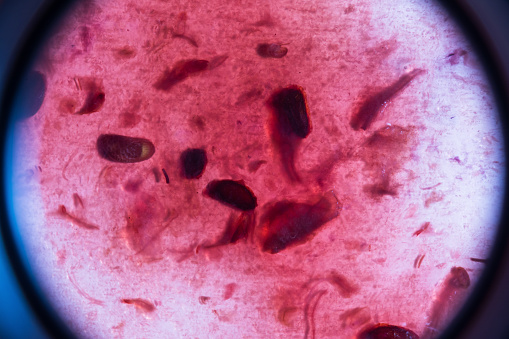

Des analyses fines immunovirologiques ont montré :

> une augmentation significative des réponses immunitaires de type TCD8 vis-à-vis du virus ;

> une diminution drastique et persistante du réservoir viral mesuré par la quantité d’ADN VIH dans les cellules du patient, c’est-à-dire du matériel génétique du virus VIH intégré dans les chromosomes cellulaires.